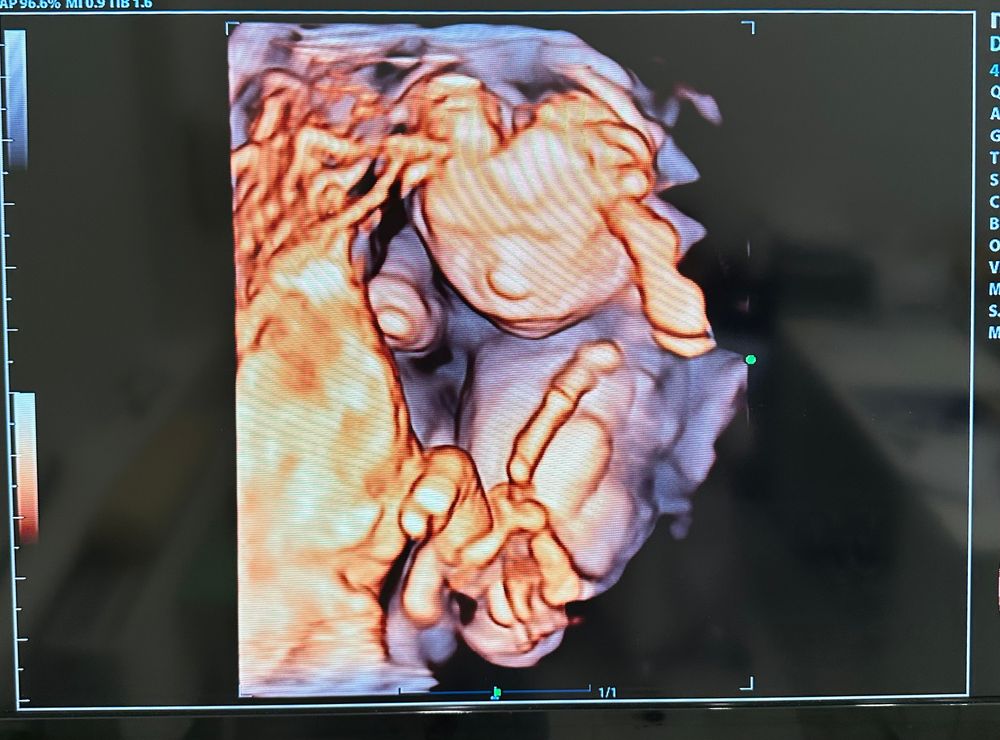

Всё у нас по узи хорошо 🙌🏻 Пальчики на месте, верхняя губа в порядке, кость носа 4,1мм.

Весит малышка 149г.